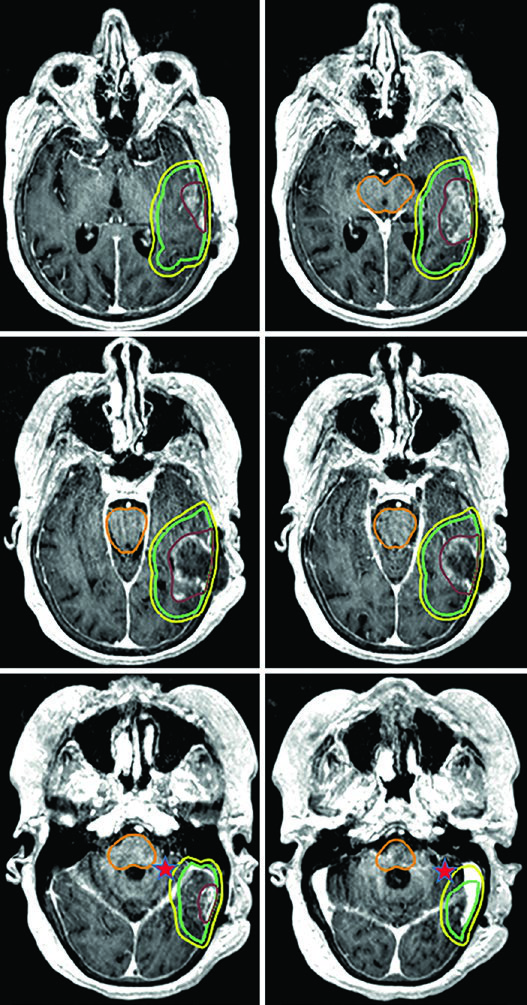

Glioma de Alto Grau: Volumes-Alvo e Fracionamento

Pacientes com astrocitoma de alto grau e oligodendroglioma passam por ressecção cirúrgica máxima para diagnóstico, caracterização molecular e citorredução. O tratamento padrão combina radioterapia conformacional fracionada com quimioterapia — seja concomitante, adjuvante ou ambas.

A dose padrão para gliomas de alto grau é de 59,4–60 Gy com fracionamento convencional. Para pacientes idosos, frágeis ou com performance status limitado, esquemas hipofracionados são uma alternativa validada: 40,05 Gy em 15 frações ou até 25 Gy em 5 frações, com margens reduzidas (0,5–1 cm). A tabela a seguir resume os volumes recomendados por tipo tumoral.

| Glioblastoma | Cone-down: PTV1 46 Gy (2 Gy/fx), PTV2 60 Gy (2 Gy/fx); ou SIB: PTV1 50–51 Gy (1,67–1,7 Gy/fx), PTV2 60 Gy (2 Gy/fx) | GTV1: volume T2/FLAIR; GTV2: cavidade + tumor residual na T1 pós-contraste | CTV1: 2 cm restrito anatomicamente; CTV2: 2 cm restrito | 0,3–0,5 cm |

Um ponto prático fundamental: as expansões anatomicamente restritas significam que o CTV não cruza a linha média, não invade a cisterna pré-pontina, não se estende pelo crânio e não ultrapassa o tentório para a fossa posterior. No entanto, tratos em risco para disseminação tumoral contralateral — como o joelho do corpo caloso — devem ser incluídos. Essa nuance aparece claramente nos casos de glioblastoma frontal em que o tumor se aproxima do corpo caloso.

Para situações ainda mais agressivas em termos de prognóstico, o regime ultra-hipofracionado de 25 Gy em 5 frações é uma opção, com margens de 0,5 cm do GTV para o CTV. Um exemplo típico é o glioblastoma cerebelar — a cóclea e o tronco encefálico ficam visíveis e servem como referência direta na dosimetria.

Já o gliossarcoma segue paradigma semelhante ao do glioblastoma. Dois volumes sequenciais costumam ser empregados — o primeiro baseado no FLAIR (46 Gy) e o segundo na T1 pós-contraste (60 Gy), com expansões de CTV de 1,5 cm anatomicamente restritas.